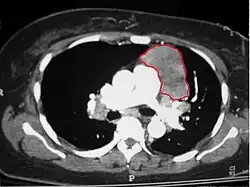

CT scan of the chest revealing a large necrotic mass in the left anterior mediastinum (indicated by the red line). Histology later established the diagnosis of a thymoma.

When a thymoma is suspected, a CT/CAT scan is generally performed to estimate the size and extent of the tumor, and the lesion is sampled with a CT-guided needle biopsy. Increased vascular enhancement on CT scans can be indicative of malignancy, as can be pleural deposits.[2] Limited biopsies are associated with a very small risk of pneumomediastinum or mediastinitis and an even-lower risk of damaging the heart or large blood vessels. Sometimes thymoma metastasize for instance to the abdomen.[6]

The diagnosis is made via histologic examination by a pathologist, after obtaining a tissue sample of the mass. Final tumor classification and staging is accomplished pathologically after formal surgical removal of the thymic tumor.